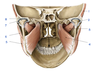

A

Zygomatic process (of temporal bone)

B

Tubercle (of temporal bone)

C

Groove for deep temporal vessels (of temporal bone)

D

Postglenoid tubercle (of temporal bone)

E

Supramastoid crest (of temporal bone)

F

Suprameatal spine (of temporal bone)

G

Opening of external acoustic meatus (of temporal bone)

H

Tympanomastoid fissure (of temporal bone)

I

Mastoid process (of temporal bone)

J

Tympanic part (of temporal bone)

K

Vaginal process (of temporal bone)

L

Styloid process (of temporal bone)

M

Angle (of mandible)

N

Ramus (of mandible)

O

Condylar process (head and neck)(of mandible)

P

Mandibular notch and coronoid process (of mandible)

Q

Anterior (surface of maxilla)

R

Infratemporal (surface of maxilla)

S

Zygomatic bone

T

Zygomatic arch

U

Frontal bone

V

Greater wing of sphenoid

W

Squamous part of temporal bone

1

Articular tubercle